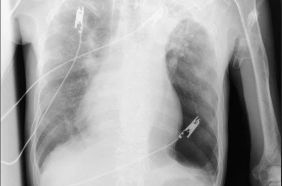

Trước băn khoăn của gia đình, BS Huyền đã tư vấn ưu tiên chụp MRI sọ não. Kết quả chụp MRI sọ não cấp đã xác định người bệnh có khối tụ máu não dưới màng cứng mạn tính kích thước lớn vùng thái dương, gây hiệu ứng khối và đè đẩy đường giữa của não. Đây là tình trạng đặc biệt nguy hiểm, bởi khối tụ máu có thể tiến triển âm thầm trong nhiều tuần với triệu chứng kín đáo như chậm chạp, giảm trí nhớ, rối loạn ngôn ngữ nhưng có nguy cơ cao dẫn đến liệt vận động, tụt kẹt não, hôn mê và tử vong nếu không được xử trí kịp thời

Ngay sau khi có kết quả chẩn đoán hình ảnh, ông P.V.D được chuyển sang chuyên Khoa Phẫu thuật thần kinh sọ não để phẫu thuật cấp cứu lấy bỏ tụ máu, giải phóng chèn ép nhu mô não. Đồng thời, người bệnh được chỉ định điều trị thuốc kháng động kinh do đã có nhiều cơn co giật rõ ràng trước đó. Sau can thiệp, tình trạng ý thức cải thiện tốt, không xuất hiện cơn co giật.